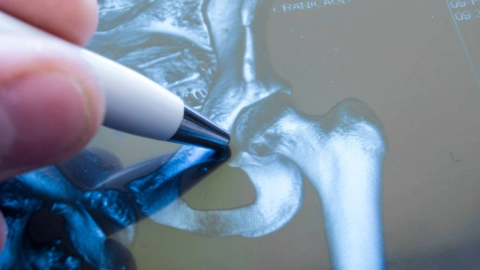

Wenn ältere Menschen stürzen, ziehen sie sich oft einen Knochenbruch (Fraktur) nahe der Hüfte zu, zum Beispiel einen Oberschenkelhalsbruch. Solch ein Bruch muss in der Regel operiert werden.

Mehr erfahren

Eine Hüftarthrose beginnt häufig schleichend. Schmerzen bei Bewegung gehören zu den ersten Anzeichen. Die wichtigsten Maßnahmen sind Bewegungstherapien und die Einnahme von NSAR-Schmerzmitteln.

Mehr erfahren